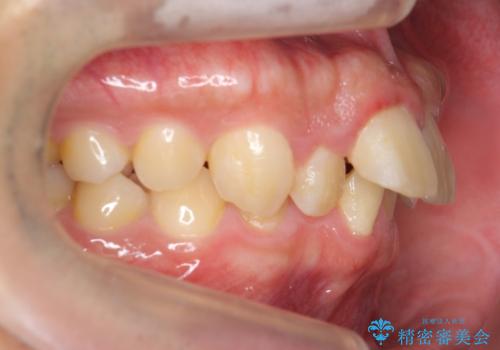

- 前歯の前突を主訴に来院。

上の歯並びが前方にずれていました。

上顎は歯を抜かずに、奥歯を後ろに下げる治療を行っています。

また、過蓋咬合(深いかみ合わせ)で食いしばりがきつく、歯の移動には大変時間がかかりました。